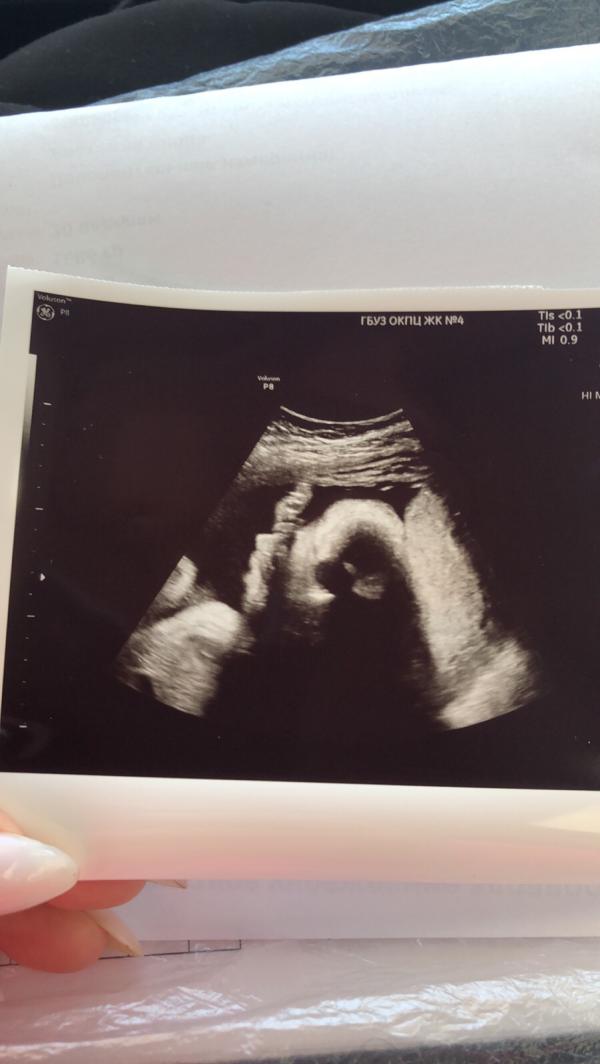

Судя по его характеру-там растёт моя копия😀 активный совёнок, шилопоп, сильный и довольно вредный 😌 на узи не даёт сделать нормального фото, то отворачивается, то руки выставляет…ничего, до нашей встречи осталось совсем немного😌